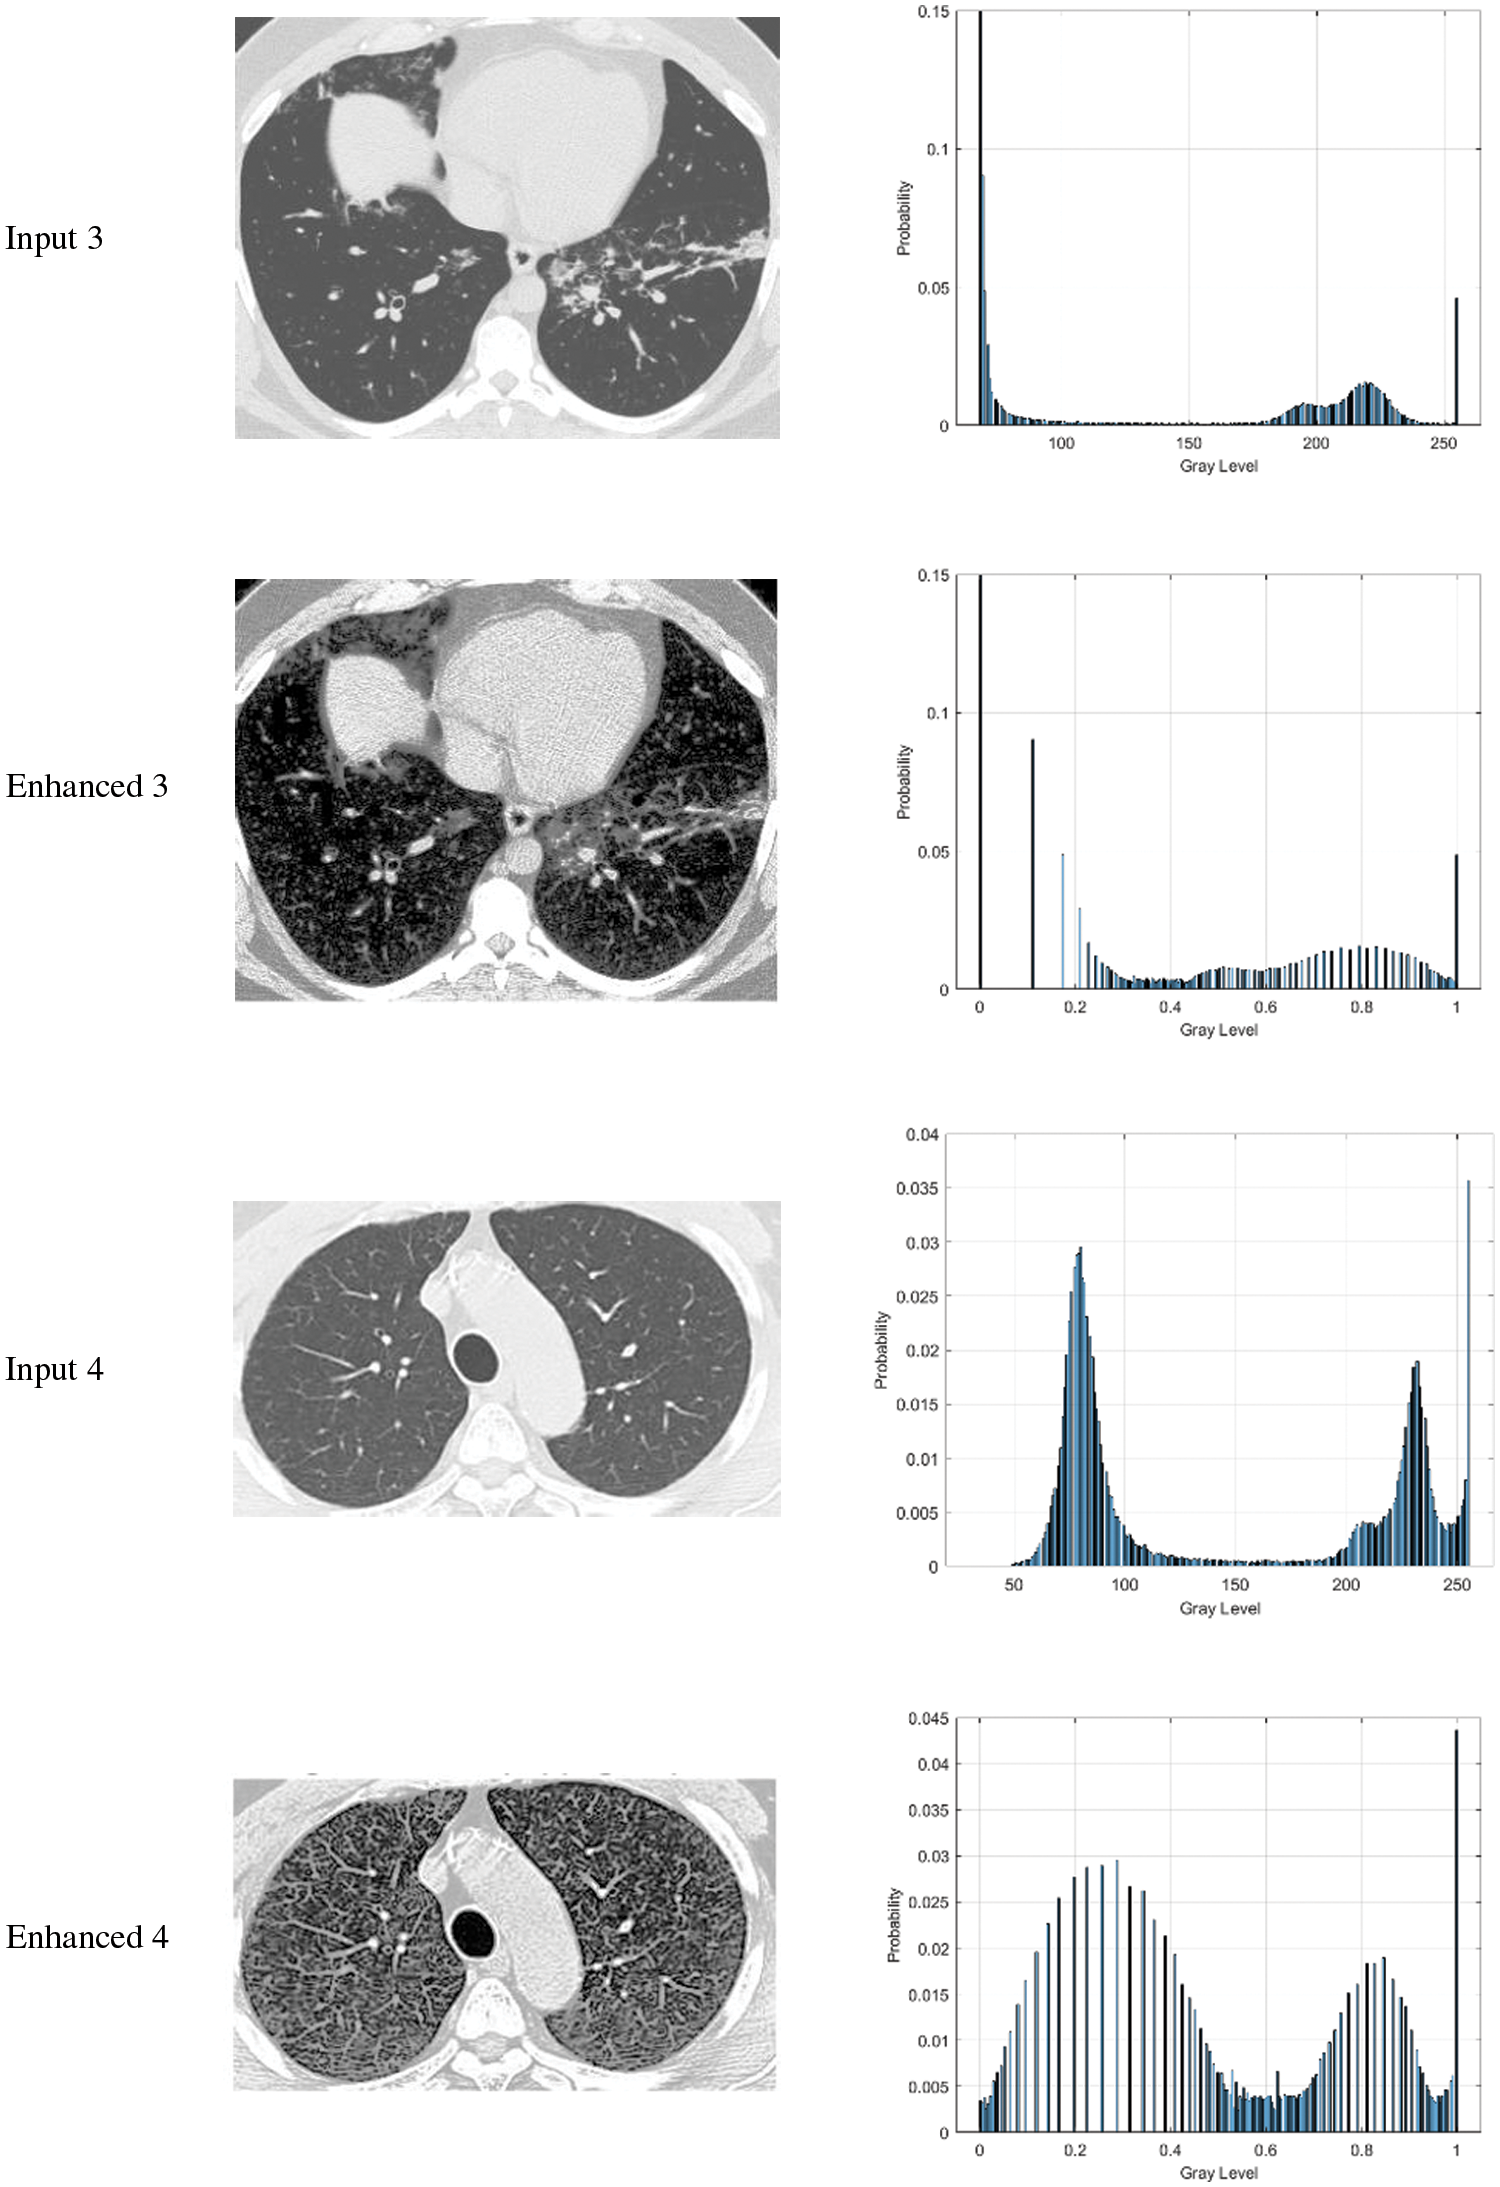

Figure 3: The results of the proposed and existing enhancement models. (A) Input image, (B) Al-Shamasneh et al. [4], (C) Al-Ameen et al. [15], (D) Fu et al. [16], (E) Raghunandan et al. [3]. (F) Ibrahim et al. [6], (G) proposed method

In Fig. 3, the proposed and existing techniques’ qualitative outcomes for CT image input are shown in which all the images exhibit various trends with dark and bright parts.

For the comparative analysis, we used the following existing approaches to show that the proposed enhancement model is effective as a medical picture enhancing tool. Al-Shamasneh et al. (2018) [4] developed a fractional entropy-based approach for enhancing kidney images. Al-Ameen et al. 2016 [15] proposed an MRI brain image enhancing approach. Fu et al. 2016 [16] developed a fusion-based enhancing approach for low-light photos. Raghunandan et al. 2017 [3] developed an image enhancement approach for license plates based on the Riesz fractional operator. Finally, a medical picture improvement model based on the proportional-Caputo hybrid operator's class of fractional partial differential equations (FPDEs) [6].

When existing methods’ enhancement results are compared to the proposed approach's enhancement outcomes, the proposed method outperforms the existing methods in terms of image quality. It may be seen in the instance of the existing approaches that the Al-Ameen et al. [15] Fig. 3C, and Ibrahim et al. [6] Fig. 3F techniques yield over-enhanced images, whereas the suggested method enhances the dark portions of input photos while leaving the brilliant areas alone.

Overall, the proposed model's brightness produces the structures of medical images, which often depict edges, well-defined and clear. This is due to the model's capacity to efficiently capture high frequency features. For images that are poorly lighted, the proposed approach produces reasonable visual results. This is the Mittag-Leffler sum with the fractional parameter α contribution to this study. In Tab. 1, the quantitative outcomes of the proposed enhancement method and existing enhancement models, are summarizes.